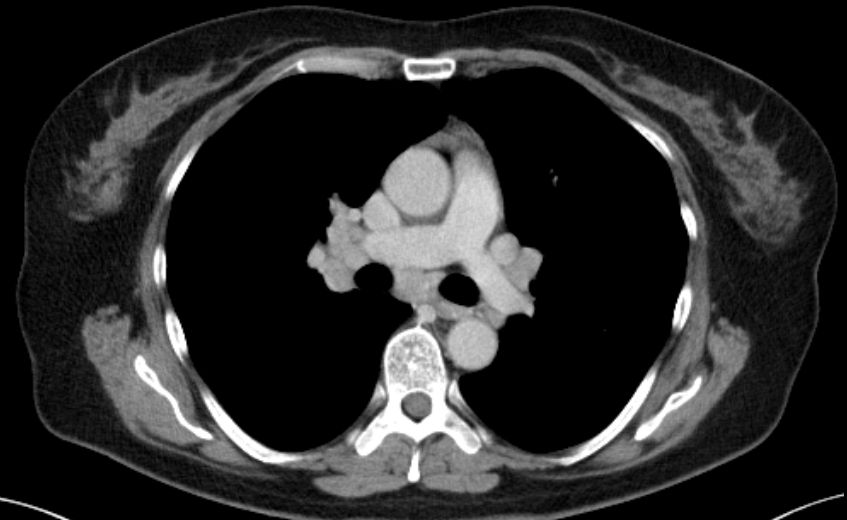

| Hilus- Lymphknoten | oft bihiläre Lymphadenopathie | 57-jährige Frau, die vor 15 Jahren ein Rektumkarzinom und vor einem Jahr ein Coecumkarzinom T4 N2b(14/14) Mo hatte. Beim Restaging vergrößerte Lymphknoten mediastinal, hilär beiderseits und paraaortal. Biopsie: floride Sarkoidose.![]() | |||||||||||||||||||||||||||||||||||||||||